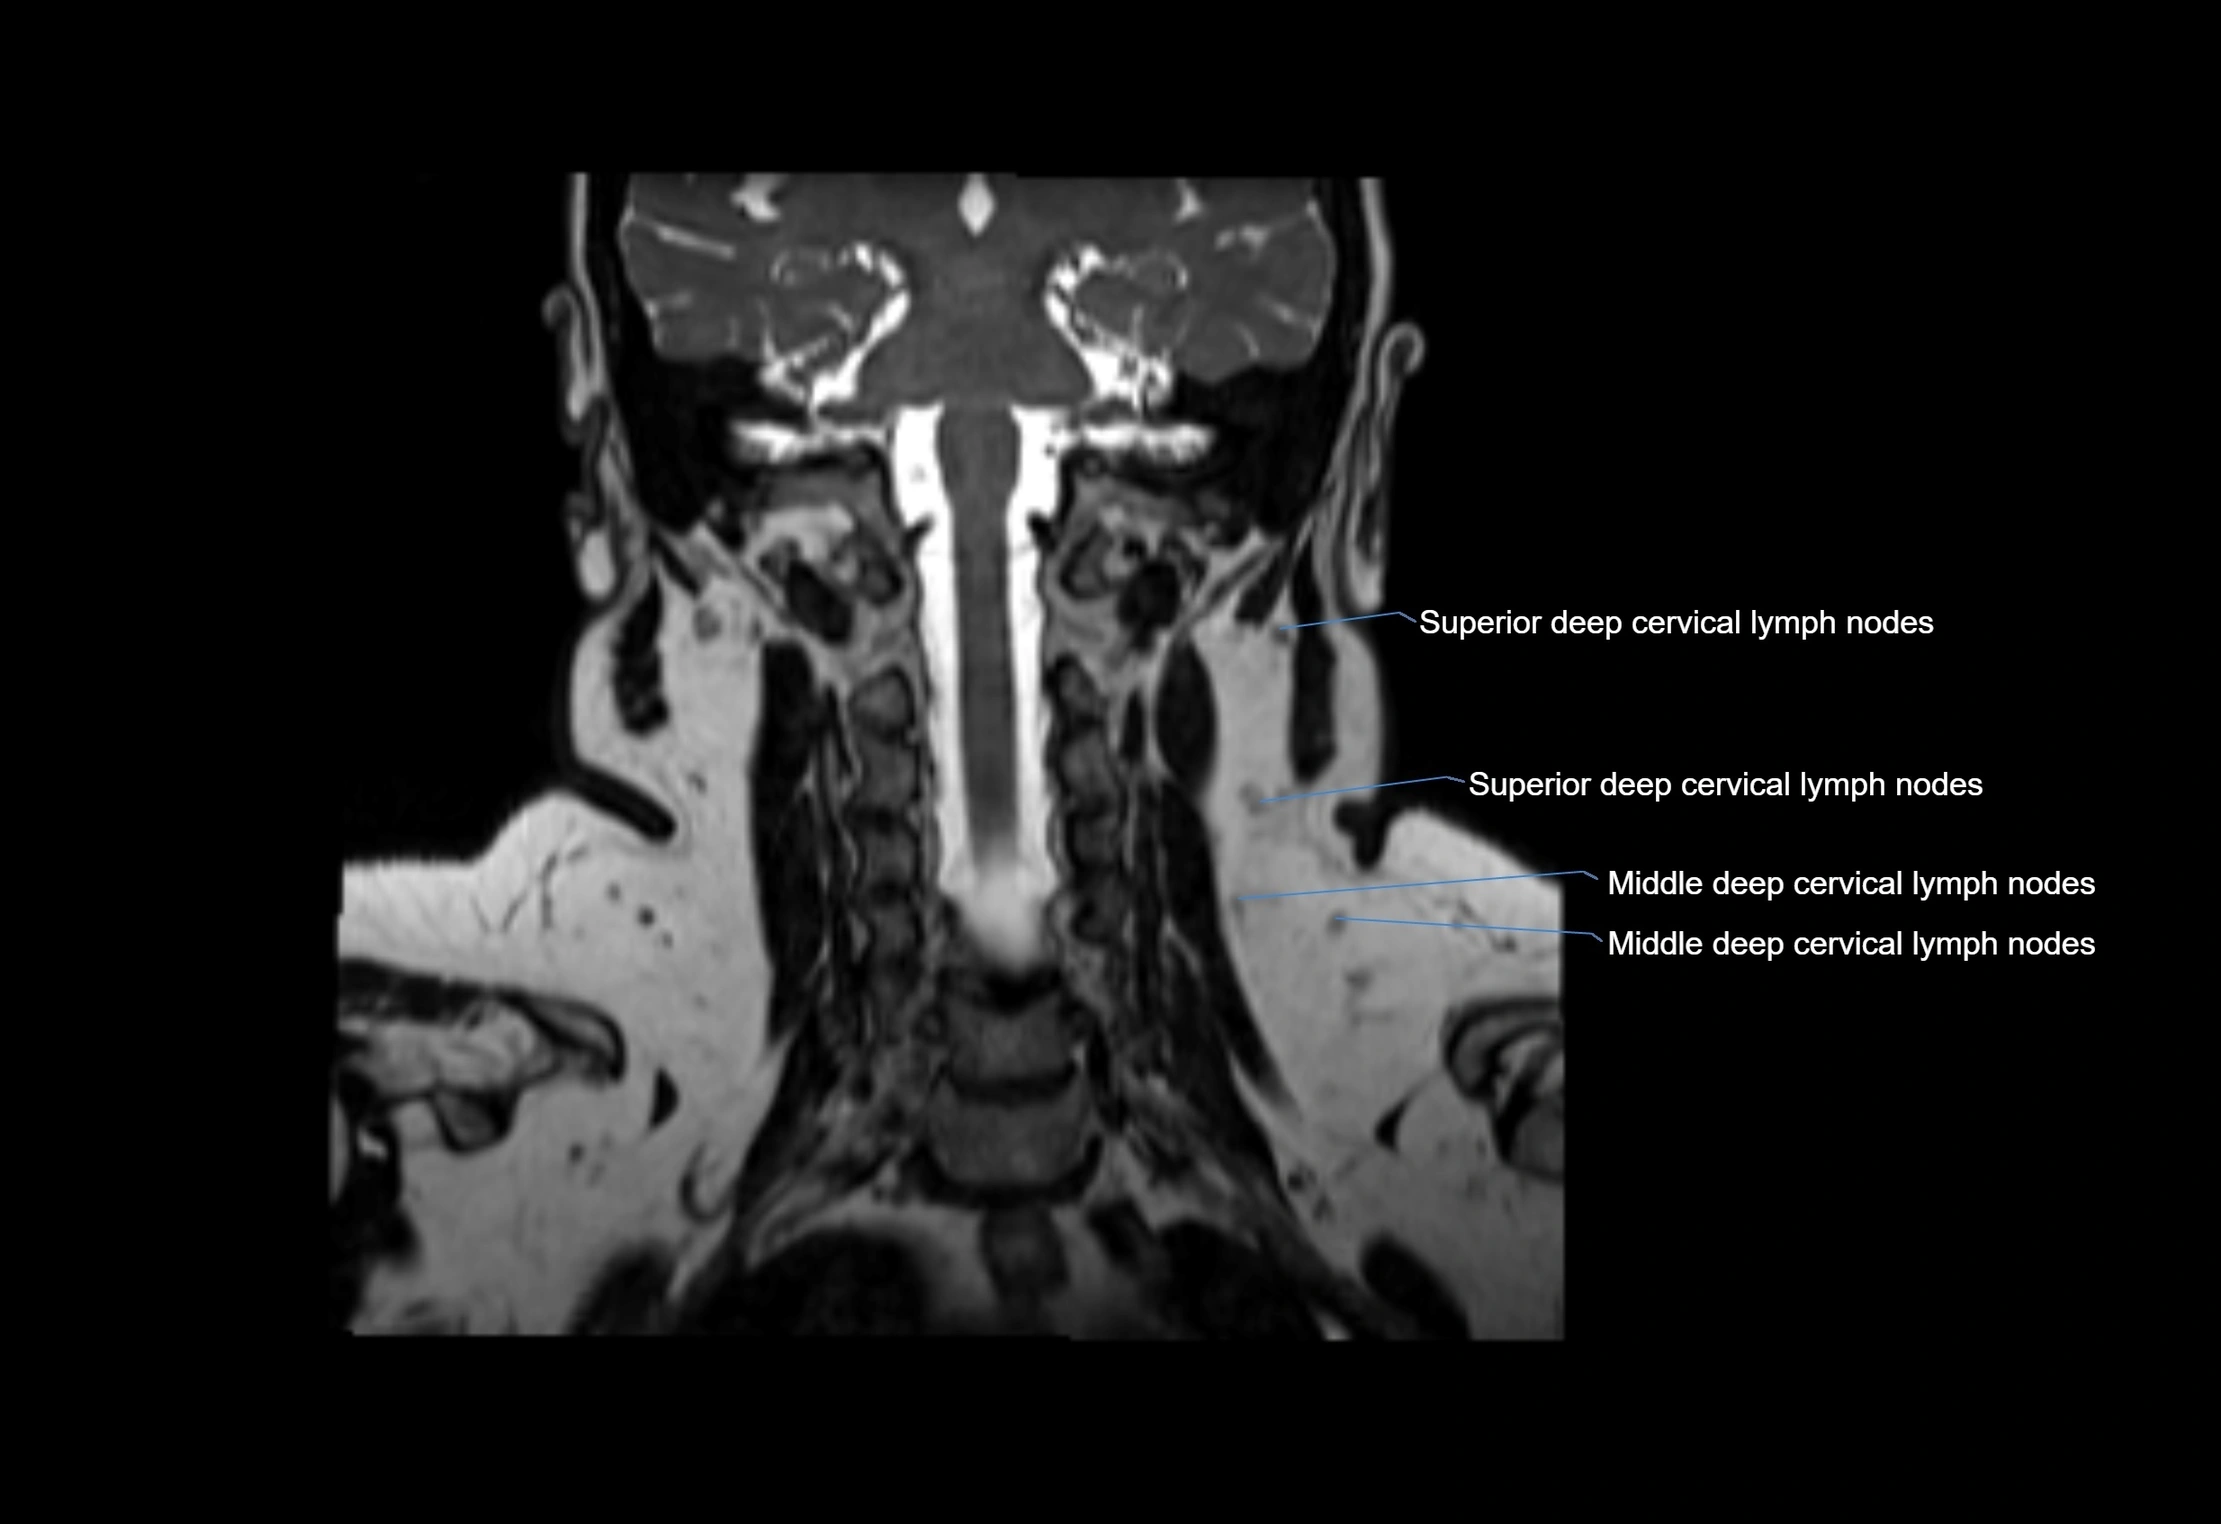

MRI Appearance

T1-weighted images:

• Normal accessory nodes appear as small, oval hypointense to intermediate signal structures within subcutaneous fat

• Surrounded by hyperintense fat, enhancing contrast for visualization

• Pathological nodes may appear enlarged or rounded, sometimes with cortical thickening

T2-weighted images:

• Nodes show intermediate signal, with surrounding fat bright

• Useful for detecting edema, inflammation, or infiltration

• Fatty hilum may appear slightly hyperintense relative to cortex

MRI images

image